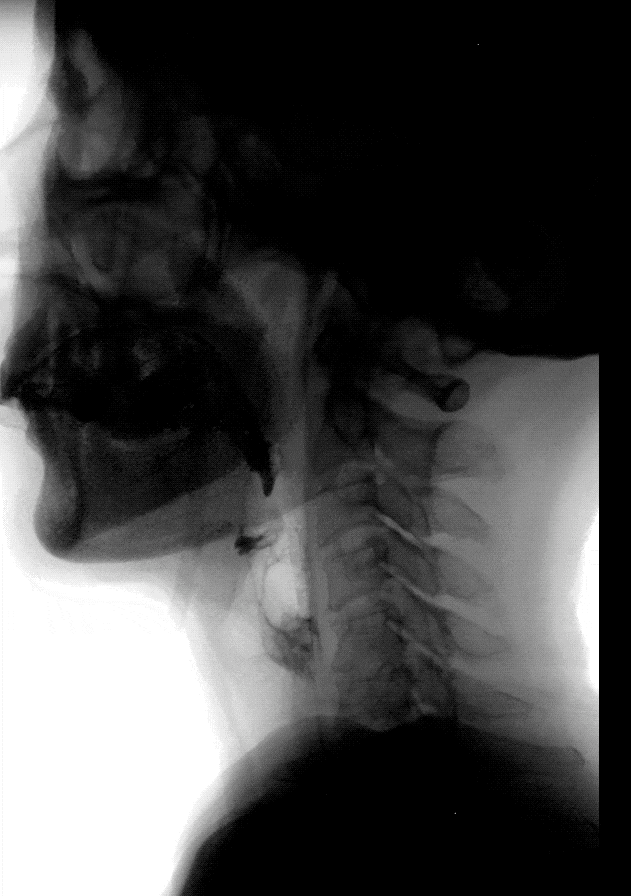

吞咽康復(fù)治療是一個綜合性的過程,涵蓋評估、功能訓(xùn)練、飲食調(diào)整及心理干預(yù)等多個方面。首先,通過專業(yè)的評估,了解患者的吞咽功能狀態(tài),明確障礙的類型和程度。隨后,根據(jù)評估結(jié)果,制定個性化的康復(fù)治療方案。治療方案可能包括口腔肌肉訓(xùn)練,以增強(qiáng)口腔肌肉的力量和協(xié)調(diào)性;吞咽姿勢調(diào)整,幫助食物順利通過咽部;電刺激治療,提高吞咽反射的敏感性;以及吞咽訓(xùn)練,逐漸增加吞咽的難度和量。